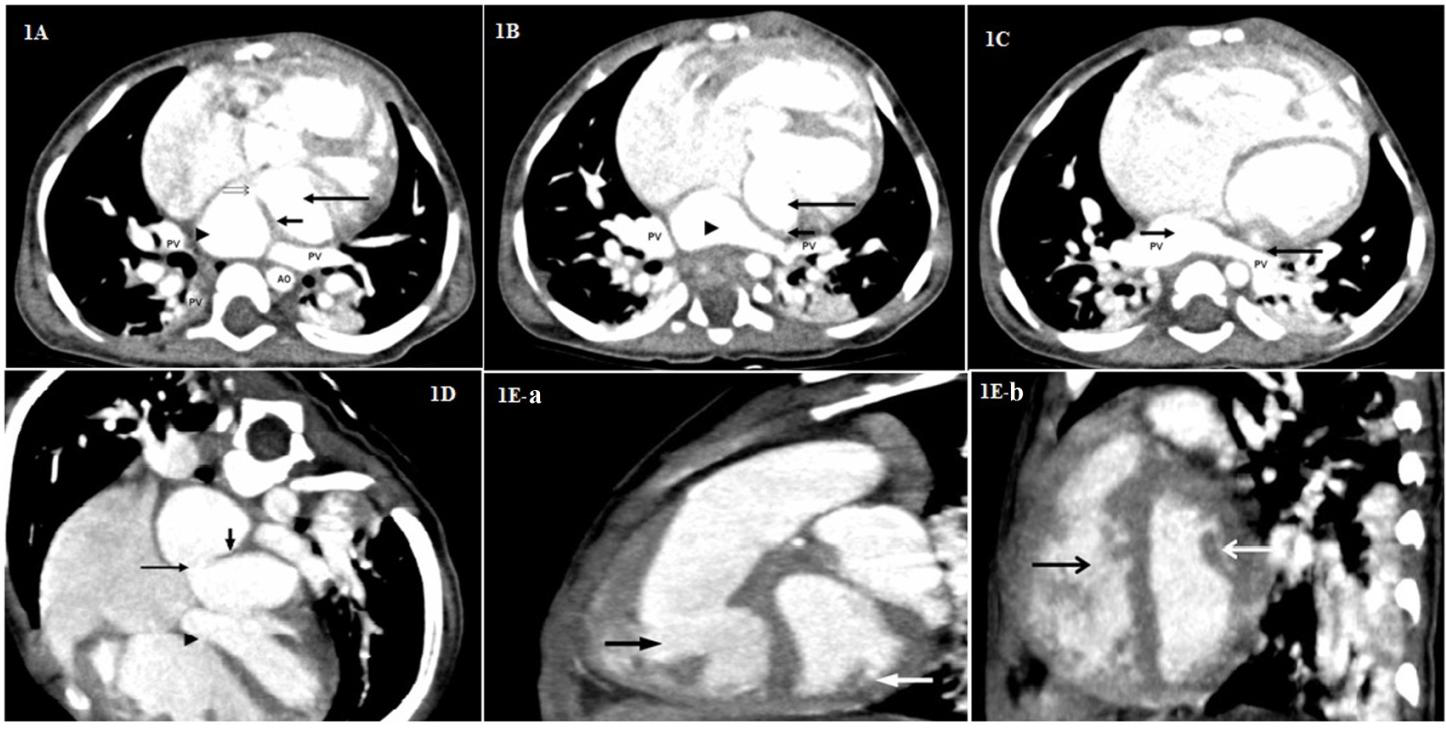

Further, in view of complex cardiac anomalies CT angiography was performed. Multi detector computed tomography (MDCT) study depicted a thick membrane (Figure 1A-1E) in left atrium with its compartmentalization. Aortic coarctation, membranous VSD, PDA, persistent left SVC (draining into coronary sinus) were well demonstrated. Two normal papillary muscles were seen. In addition polysplenia (Figure 2A- 2D) was seen in the absence of signs of heterotaxy syndrome. Based on the above findings diagnosis of cor triatriatum sinister was concluded.

Since the end of the 20th century, echocardiography has been the mainstay of imaging for the diagnosis of cor triatriatum [9,10]. The echocardiogram includes study of the 2D pattern of the membrane, analysis of turbulent flow on color Doppler and determination of any gradient across the membrane on continuous wave Doppler. Furthermore, the existence of co morbid congenital cardiac anomalies can be studied by echocardiography. A retrospective review study showed that transthoracic echocardiography has 98% accuracy in diagnosis cor triatriatum [11].Currently, advanced sophisticated imaging techniques like cardiac CT have been extensively employed for the non invasive evaluation of coronary artery disease. Mounting clinical evidences report the diagnosis of cor triatriatum using CT [12,13]. Our case is unique in that it is the first report of 64- slice multi detector computed angiography revealing cor triatriatum with least common associations of PDA, VSD and polysplenia. Studies reveal that cardiac CT has potential benefits with safety and economical aspects when compared to the conventional coronary angiography in the non-invasive evaluation of coronary artery disease [14]. In addition, high spatial and temporal resolutions images in cardiac CT provide information regarding cardiac anatomy, wall motion and myocardial perfusion. In this regard, our case demonstrates the utility of CT in diagnosing the underlying complex anatomic abnormalities in cor triatriatum.